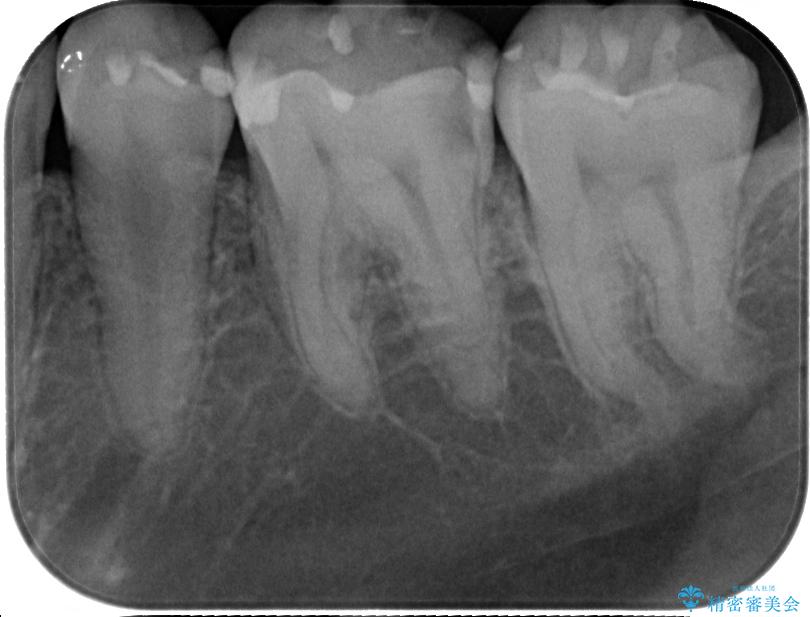

- 当院で矯正治療を終えて、左下が虫歯になっている気がするとのことで来院された患者様です。レントゲン検査の結果、コンポジットレジンによる修復箇所が複数行われており、詰め物の下に虫歯を認めました。